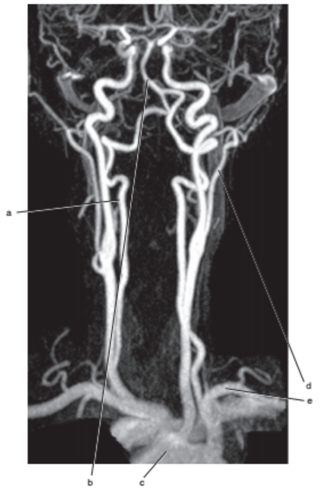

What is letter l ?

Common carotid

What is letter e ?

Subclavian artery

What is letter f ?

Common carotid artery

Vertebral artery

What is letter c ?

Aortic arch

What is letter b ?

Thyroid gland

What is letter a ?

Internal jugular vein